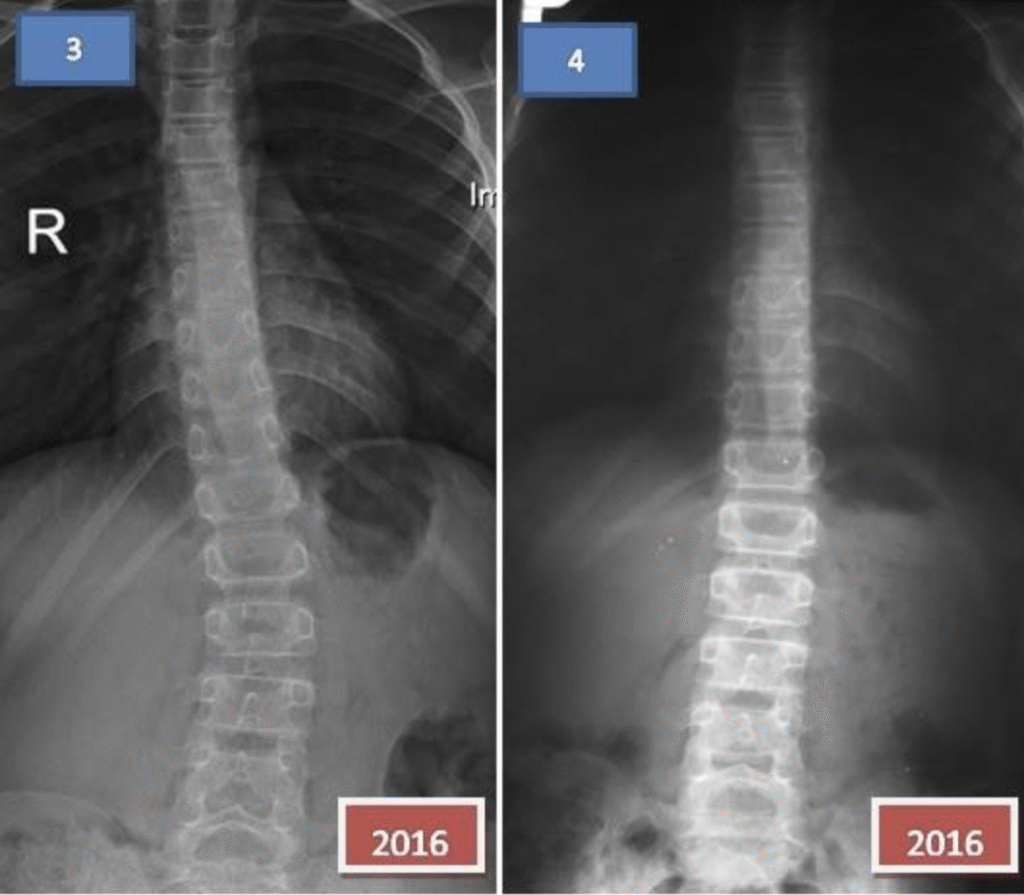

Klaudia – 9 lat

Terapia prowadzona w okresie 19.12.2014 – 16.04.2015 (20 zabiegów) Częstotliwość zajęć – 10 zabiegów 2 x tydz., 10 zabiegów 1 x tydz.

Gabrysia – 11 lat

Terapia prowadzona w okresie 26.08 – 09.11.2015 (18 zabiegów) Częstotliwość zajęć – 2 x tydz.